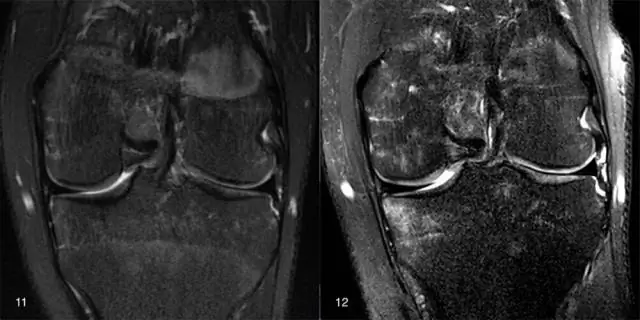

- МРТ